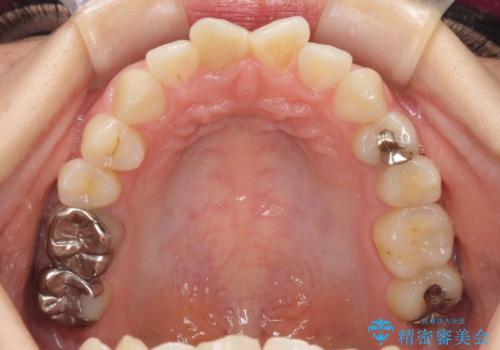

根管治療について

保険根管治療は回数がかかることが多く、終了予定がわかりにくいです。

当院では、根管治療は長い時間のご予約を頂き、多くの場合2~3回で終わります。

根管治療は歯内の治療なので患者様には見えない場所ですが、ここが細菌で汚染されると激しい痛みや長引く違和感の原因になります。

当院では、清潔な治療を徹底し、顕微鏡を使用した精密な治療を行っています。

症状や根管の状態により、治療金額が異なります(5~10万円目安)。治療回数による費用負担の増減はありません。